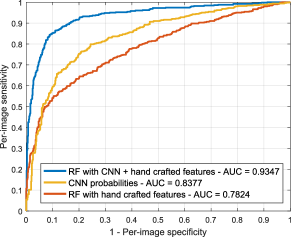

Figure 11(a) illustrates the ROC curves for DR screening on MESSIDOR, obtained using our hybrid representation and each of the approaches separately. CNN results were obtained using the network as a classifier. A series of Mann-Whitney tests () were performed to study the statistical significance of the differences in the AUC values (Hanley and McNeil, 1982). CNN features (AUC ) perform significantly better () than hand crafted features (AUC ) for this specific task, and the combination of both sources of information results in a substantially higher AUC value of 0.8932 (). Figure 11(b) shows analogous behavior for detecting patients that need referral, with the CNN performing better than the hand crafted features (), and the combined approach outperforms both individual techniques ().